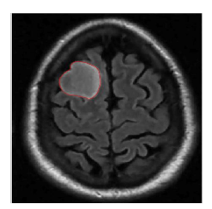

5.4 Results on brain MRI images

To achieve accurate segmentation of medical images, we have carefully tuned the parameters α, λ, and μ, which play a critical role in the performance of the DRLSE algorithm. These parameters control key aspects of the level set evolution, such as the smoothness of the contour (α), the fitting to the object boundaries (λ), and the regularization of the level set function (μ).

Using an empirical approach, we iteratively adjusted these values to obtain the best segmentation results for the images shown in Figure 10. Specifically, for brain MRIs, we found that setting α=0.5, λ=6, and μ=0.02 provided optimal segmentation results. These values effectively balance the trade-off between contour smoothness and accuracy in detecting object boundaries.

The segmentation process required several iterations to refine these parameters, highlighting the importance of adapting them to the specific characteristics of the images being analyzed. The results confirm the robustness of the DRLSE algorithm in delimiting structures in medical images.

Figure 10. Segmentation result. with the DRLSE algorithm